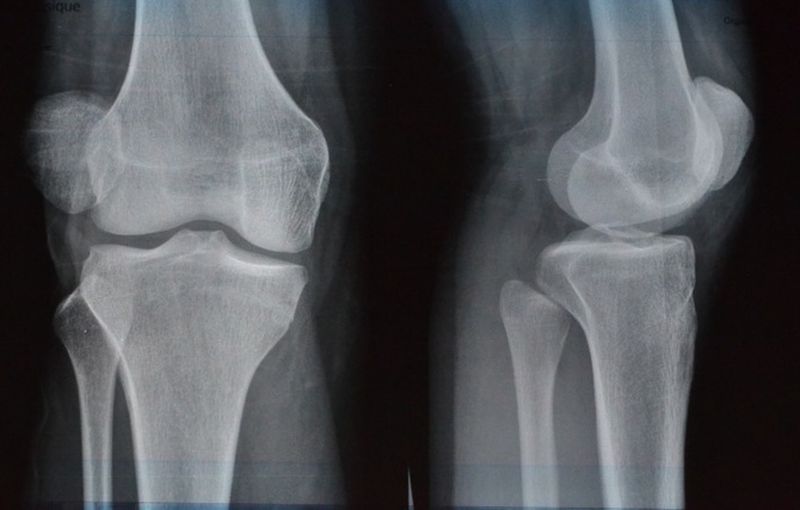

Durere de genunchi- Tendonita patelara

Tendonita patelara este o leziune ce se datoreaza solicitarii excesive ce afecteaza tendonul patelar, care se afla chiar sub rotula genunchiului. Ea leaga rotula de tibie, iar in popor este numit genunchiul ,,saritorului”.

Activitatile care necesita sarituri si aterizari frecvente suprasolicita tendonul patelar. Si rezultatul este o ruptura a tendonului de dimensiuni mici. Este des intalnita in cazul sportivilor, dar poate fi, de asemenea, rezultatul procesului de imbatranire.

Semnele si simptomele tendonitei pateliene pot include durere si sensibilitate la nivelul tendonului, ingroaarea sa, rigiditate si durere intensificata la sarituri, aterizari sau alergari. Cel care acuza o durere de acest fel ar fi indicat sa mearga la medic.